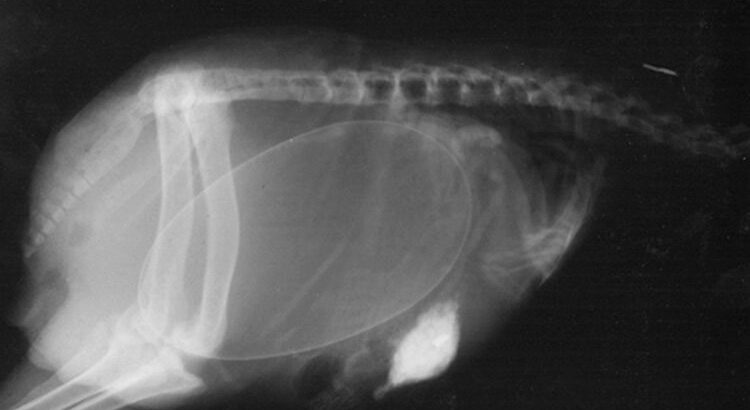

Le saviez-vous ? Les tortues font partie des reptiles à carapace, constituée d'un plastron au niveau du ventre et d'une dossière sur le dos.

Il n’est pas évident de différencier une tortue adulte mâle et une femelles. Pour certaines tortues marines, il faut avoir recourt à la génétique ou à la dissection pour déterminer le sexe.

Les tortues ont un mode de fécondation interne. Le mâle dépose les spermatozoïdes directement dans la zone génitale de la femelle pendant un accouplement (qui a lieu dans l’eau pour les tortues marines). Quand l’accouplement a lieu sur terre, ça semble souvent un non-événement pour les femelles qui continuent de marcher ou de manger… Elles sont ovipares et pondent environ une fois par an (la majorité en creusant un trou dans le sol).

Les coquilles des œufs peuvent être très souples ou très dures suivant les espèces. Elles sont poreuses, ce qui leur permet de capter l'oxygène de l'environnement et d'évacuer de l'eau.